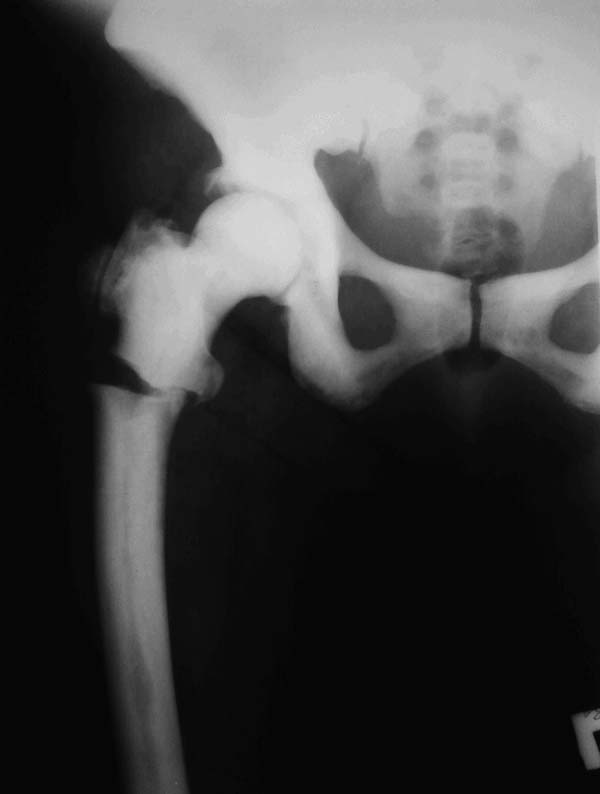

У нас есть пациентка с мраморной болезнью (остеопетроз-выявлен в детстве). К нам попала с

рентгенологической картиной патологического подвертельного перелома правой бедренной

кости. Из анамнеза - около 1,5 месяца назад появилась ноющая боль в области правого

тазобедренного сустава, периодически усиливающаяся, находилась на лечении в

ревматологическом отделении (родственники), с эффектом, боли в большей степени

купировались, самостоятельно ходила, приступая на правую ногу; однако при

транспортировки пациентки домой, а именно выхода из машины почувствовала резкую боль в

правом тазобедренном сустава, СМП доставлена в нашу клинику. Пациентка была, обследована и

подготовлена на операцию. 3 дня назад производилась: закрытая репозиция и попытка

интрамедуллярного остеосинтеза PFN Long Zimmer, однако удалось рассверлить лишь канал в

проксимальном отломке бедренной кости (частичный раскол), дистальный отломок не

поддавался расверливанию, многократные попытки, разными сверлами, разного диаметра

(канал просто отсутствует, монолитная кость). На накостный остеосинтез решено было не

переходить. Так и завершилась операция. После операции попытки наложения скелетного

вытяжения за бугристость большеберцовой кости тоже неудачны. Нужен совет: 1. Стоит ли

вообще еще пытаться оперировать, синтезировать? 2. Если стоит, то каким фиксатором лучше

сделать?